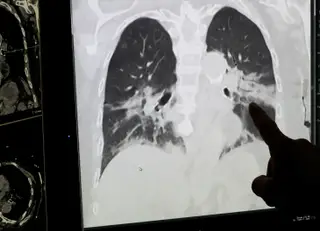

O fenómeno, conhecido como hipóxia feliz, ou silenciosa, está a intrigar a comunidade médica e a levantar questões acerca da forma como o coronavírus ataca os pulmões.

“Estamos a ver saturações de oxigénio muito baixas e as pessoas não sabem disso. Normalmente, não vemos esse fenómeno na gripe ou na pneumonia adquirida na comunidade. É um exemplo de fisiologia muito anormal a acontecer diante dos nossos olhos. ”

Mike Charlesworth, anestesista do hospital Wythenshawe, em Manchester, explica que, noutras condições pulmonares, que podem causar hipóxia grave, esses pacientes surgem, normalmente, muito doentes: "Com pneumonia ou embolia pulmonar, eles não ficam sentados na cama a conversar contigo".